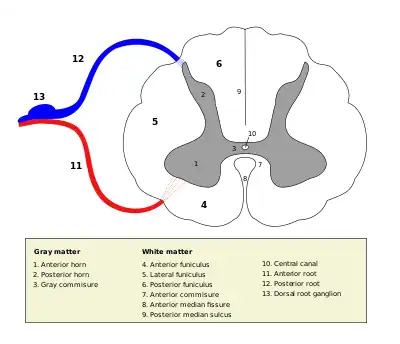

Medulla spinalis

Medulla spinalis The formation of the spinal nerve from the posterior and anterior roots